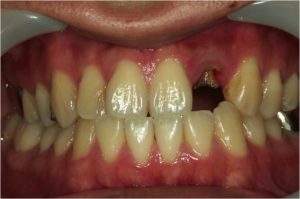

上前歯の側切歯が写真でわかるように折れていました(写真1)。

↑実際の写真1 上前歯の側切歯が写真でわかるように折れていました。